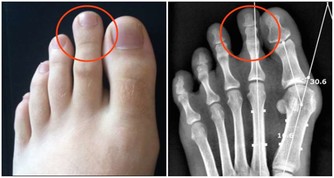

總是不喝水的人,對缺水的耐受性很強,就算身體已經缺水了,他也未必知道,而很多問題就是缺水造成的,暫且不說重大疾病的慢性蓄積,光是女人關心的皮膚好與不好,和皮膚是不是缺水有直接關係。多喝水有利於尿酸排泄,預防痛風性腎結石;多喝水還能有助於降低血液黏稠度,是預防心腦血管疾病不可缺少的一件事。